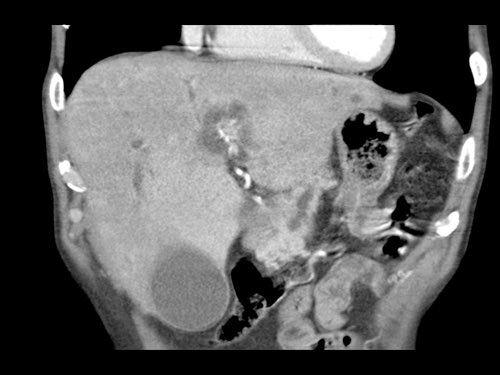

Tái tạo mặt phẳng coronal cho thấy:

- Bất thường bờ viền thành SMV được nhận thấy rõ hơn trên tái tạo coronal này (mũi tên).

- Khối u ở thân tụy (đầu mũi tên trắng).

- Huyết khối trong các nhánh bên của SMV (mũi tên xanh nhỏ).